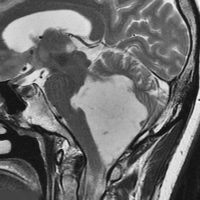

第4脳室腫瘍のMRI像

左は脳幹部腫瘍(退形成性神経節膠腫),右は小脳腫瘍(毛様細胞性星細胞腫)です。どちらも第4脳室を埋め尽くすように発育しています。これらはどちら側から発生したかが明瞭な例ですが,第4脳室腫瘍の中には脳幹部からか小脳からか解らないものもあります。でも多くは小脳側からです。脳幹部側からで注意しなければならないのは上衣腫と血管芽腫です。